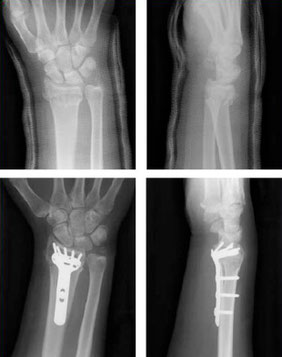

Die Versorgung von Frakturen, die aus mehreren Fragmenten bestehen und / oder eine weiche Knochensubstanz haben, werden offen über einen Hautschnitt reponiert und mit einer Platte aus Titan versorgt. Dieses ist eine der Domänen der winkelstabilen Versorgung, wobei ein Zusatzgewinde im Kopf der Schraube in einem Zusatzgewinde im passenden Plattenloch greift. Hierdurch wird eine besonders hohe Stabilität erzeugt.